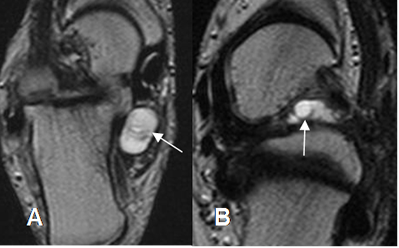

Se identifican como colecciones líquidas hipointensas en T1 e hiperintensas en T2 y STIR. (5). (Fig 141).

Fig 141. Bursitis.

RM coronal en T2. Líquido en el 1º espacio intermetatarsiano, por bursitis.